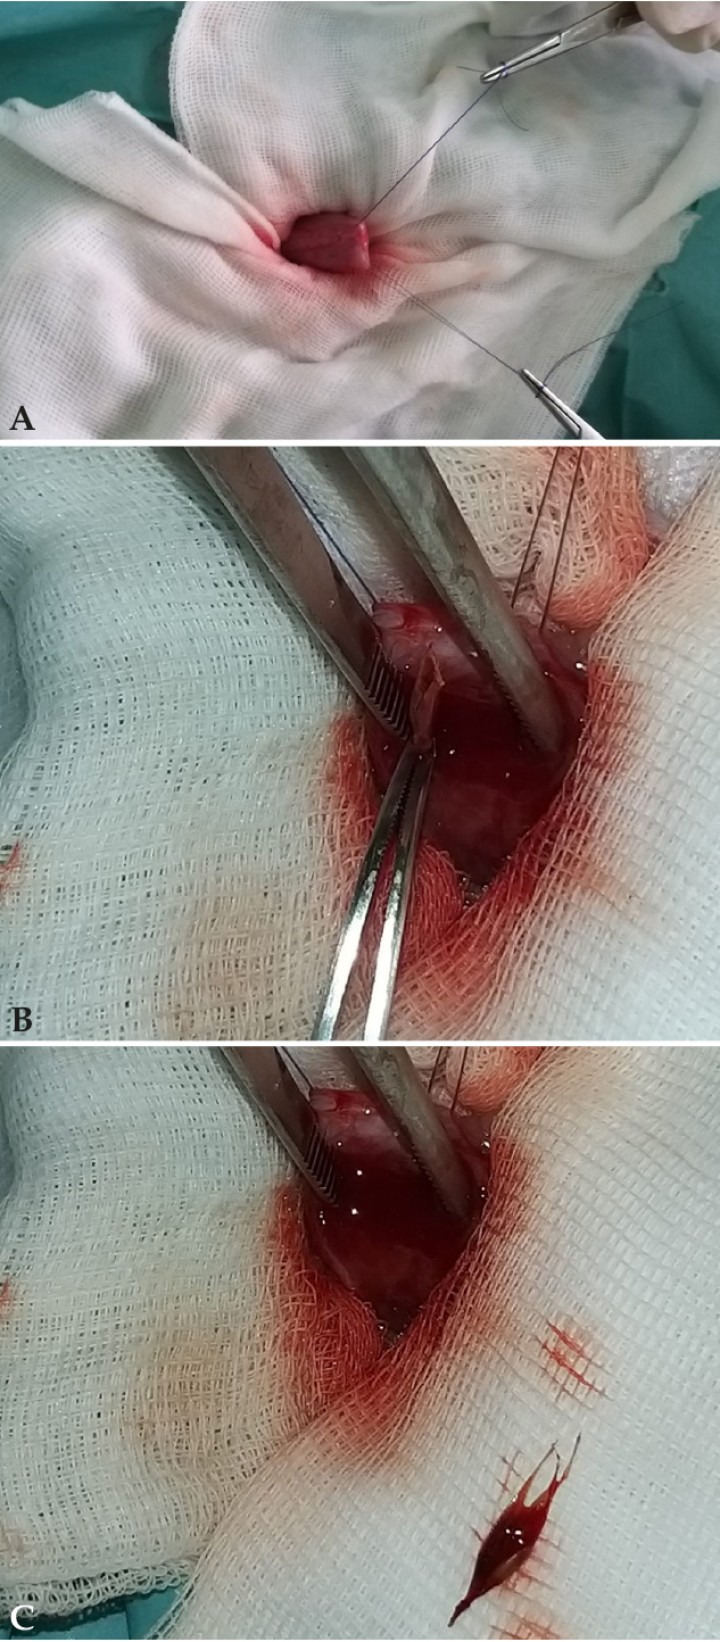

Los propietarios cancelaron la cita de la revisión debido a factores personales y a la mejoría de la sintomatología clínica. Dos días después la hematuria del paciente empeoró drásticamente y acudieron a la consulta. En ese momento se repitió la ecografía abdominal, evidenciándose una vejiga distendida con una pared vesical engrosada y la aparición de una estructura lineal intraluminal compatible con un cuerpo extraño vesical (Fig. 3). Se realizó una cistocentesis y se remitió la muestra para hacer un urocultivo.

<p>(<strong>A</strong>) Imagen ecográfica de un corte sagital de la vejiga, apreciándose una estructura ramificada hiperecogénica con aspecto de espiga en su interior. (<strong>B</strong>) Imagen ecográfica de un corte sagital de la vejiga, apreciándose desde otro ángulo la estructura hiperecogénica ramificada compatible con cuerpo extraño de origen vegetal (espiga).</p>

Figura 3

(A) Imagen ecográfica de un corte sagital de la vejiga, apreciándose una estructura ramificada hiperecogénica con aspecto de espiga en su interior. (B) Imagen ecográfica de un corte sagital de la vejiga, apreciándose desde otro ángulo la estructura hiperecogénica ramificada compatible con cuerpo extraño de origen vegetal (espiga).